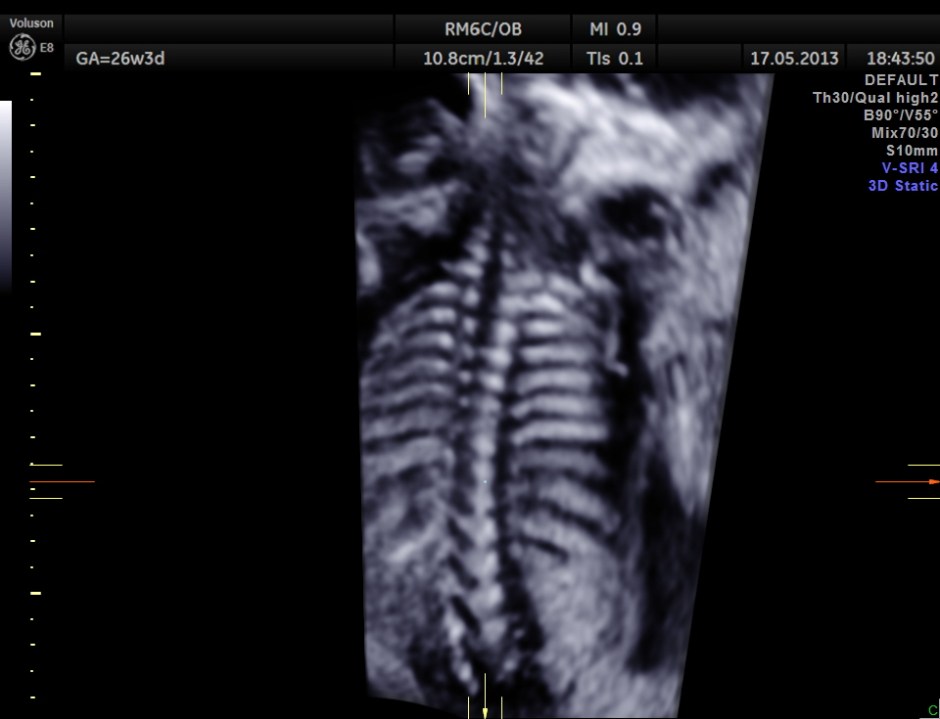

The following are 3 D reconstructed sagittal and coronal images .

The following images show the spine.